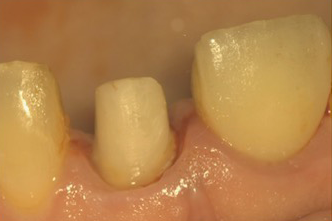

根管治療の後は、歯に土台を立て、最終的に被せ物の処置を行っていきます。被せ物には保険診療と自費診療どちらもありますが、それぞれで土台作りのアプローチが異なります。

自費の被せ物をご選択いただいた場合、土台も自費診療で作製し、根管治療と同じレベルの徹底した衛生管理を実施。細菌感染を防ぎ、歯の寿命をさらに延ばせるよう配慮しています。

自費診療においては、土台を作る工程でも細菌感染が生じないようラバーダム防湿を施し、下記の工程を行います。

マイクロスコープ(歯科用の顕微鏡)を用いて内部の残留物などを確認しキレイにしていきます。

②次にマイクロスコープで確認しながら、土台の材料を流し込みます。

③仮歯が入れられるように、土台の形を整えます。

こうした精密な処置により、長期的な予後の向上を目指しています。